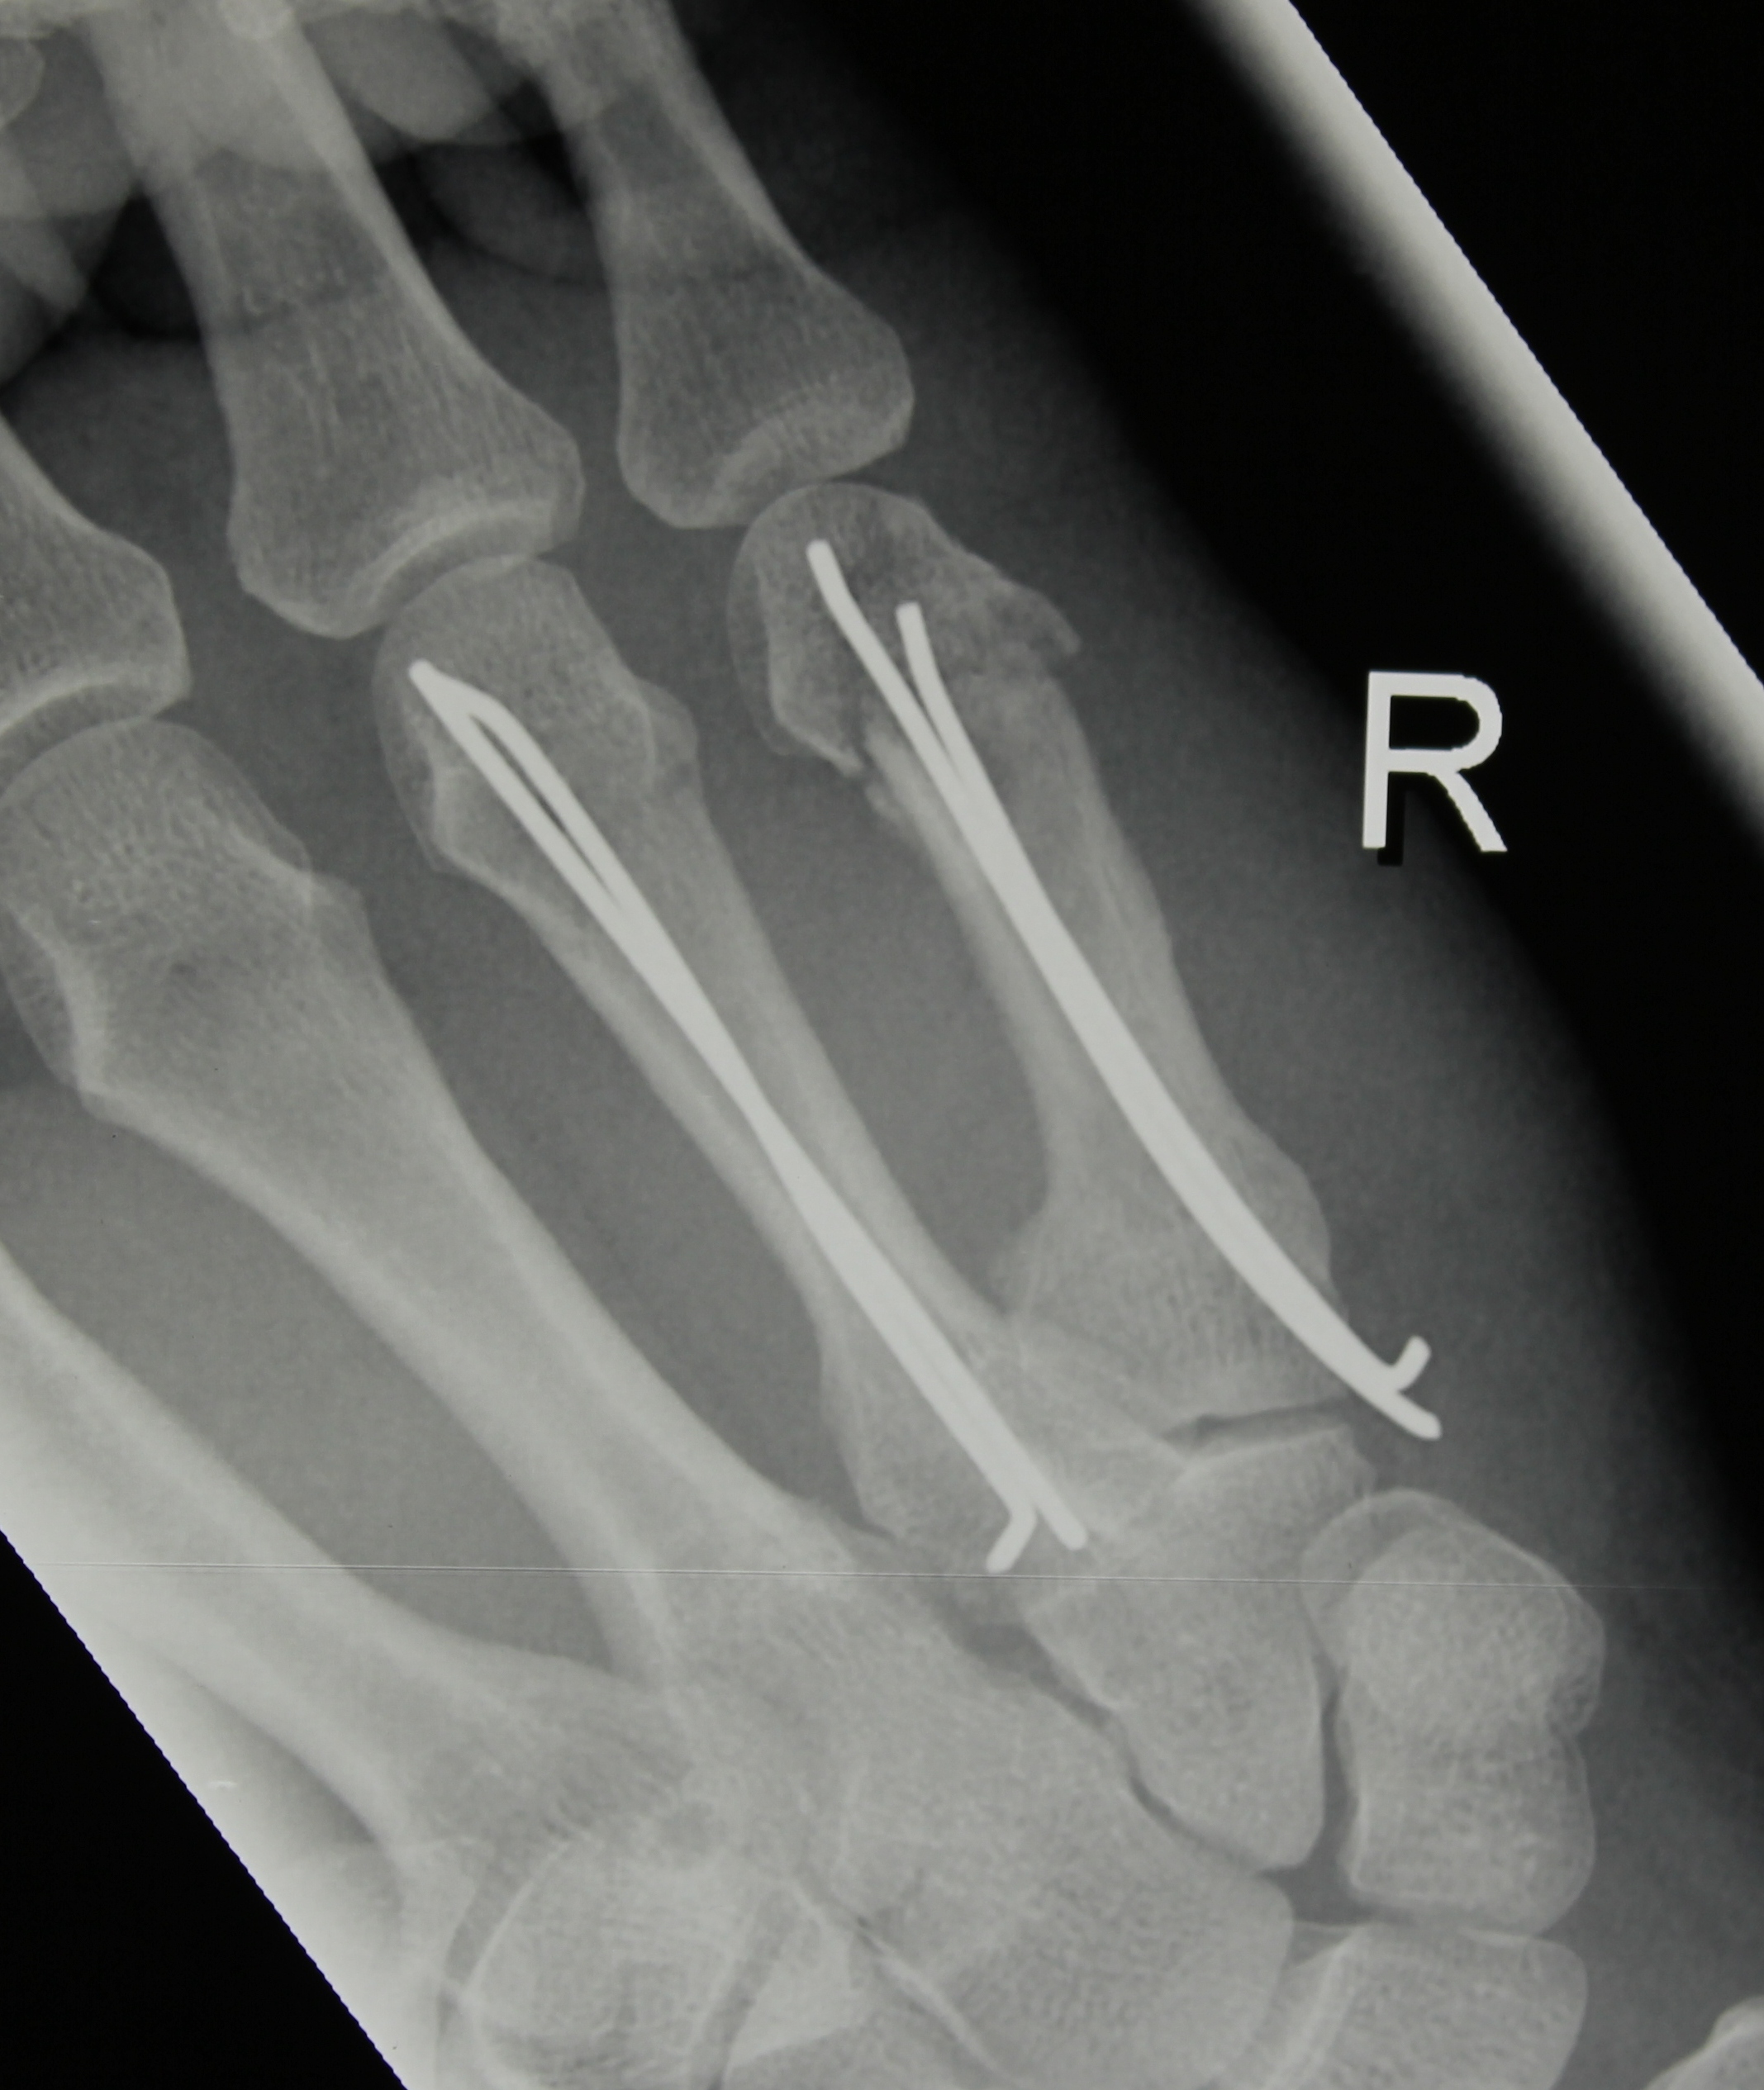

Hsu LP, Schwartz EG, Kalainov DM, Chen F, Makowiec RL. Complications of K-wire fixation in procedures involving the hand and wrist. J Hand Surg Am 2011;36(4):610-6.

Gillis JA, Lalonde J, Alagar D, Azzi A, Lalonde DH. K-wire fixation of closed hand fractures outside the main operating room does not increase infections. Plast Reconstr Surg Glob Open 2022;10(11):e4679.

Ridley TJ, Freking W, Erickson LO, Ward CM. Incidence of treatment for infection of buried versus exposed Kirschner wires in phalangeal, metacarpal, and distal radial fractures. J Hand Surg Am 2017;42(7):525-31.